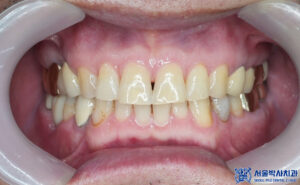

이렇게 전체적인 치료가

마무리 되었습니다.

마무리 후 사진입니다.

환자분께서는 발치나 임플란트 이후에도

정말 안 아프다며 괜찮다고

피드백을 주셨습니다.

그리고 어금니 쪽에 이전에 진행했던

보철보다 훨씬 마음에 드신다며

크라운과 임플란트 보철 모두

심미적으로 자연스럽고

꼭 맞게 잘 설계되었다며

매우 좋아해주셨습니다.